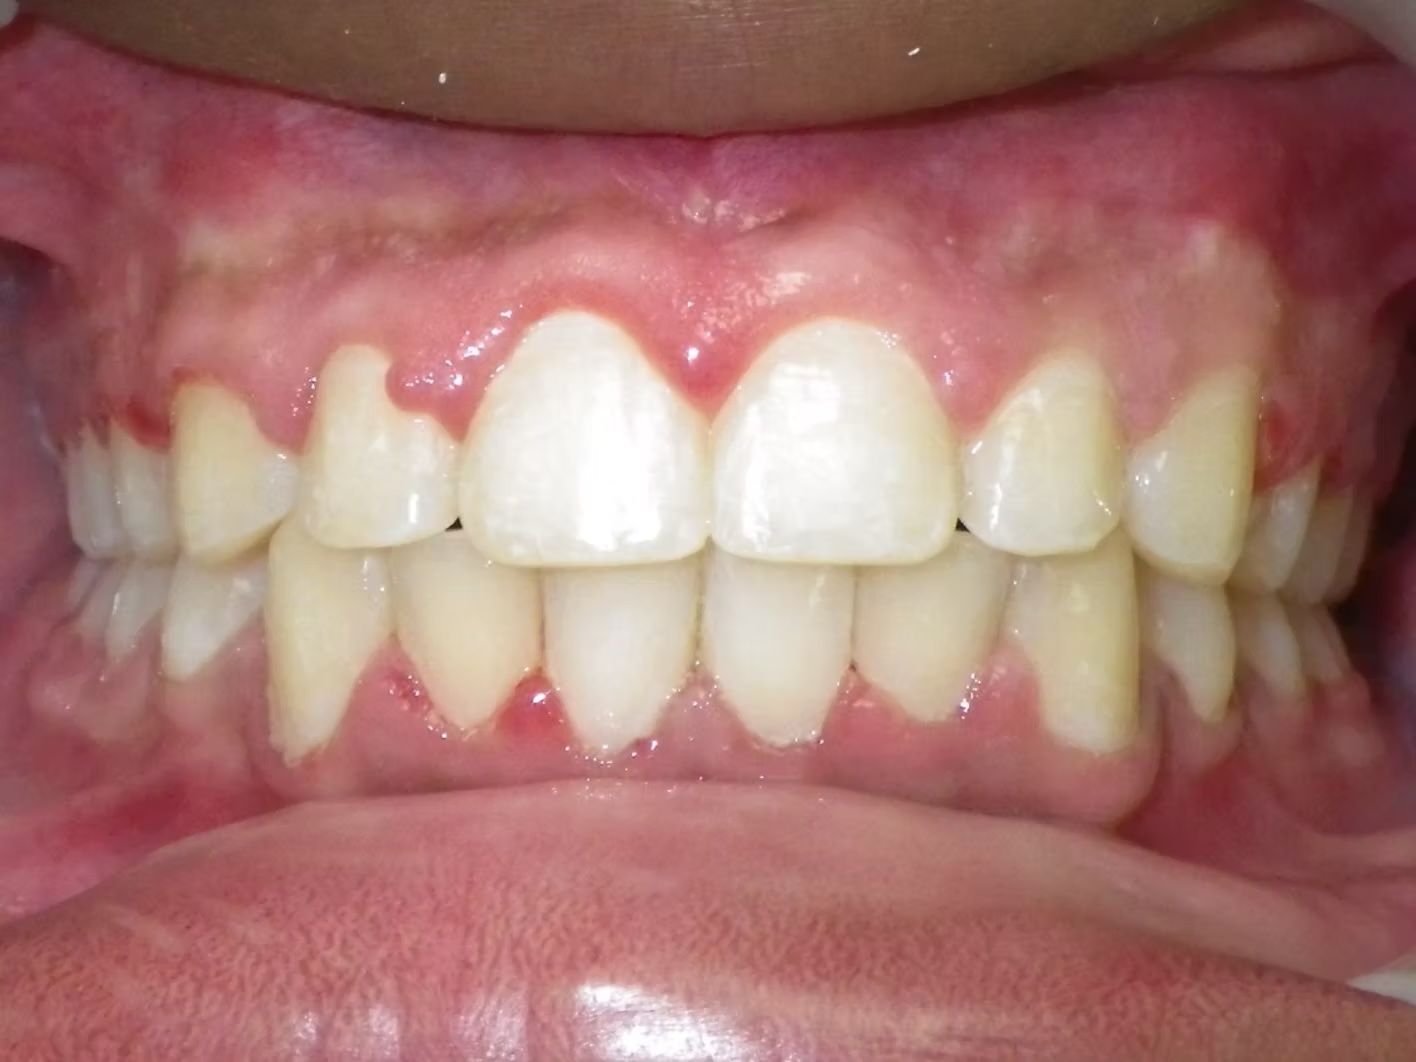

Emily

Emily didn't like how her top teeth were turned in and the lower teeth were crowded. Her bite was slightly off on both sides. Emily just needed upper and lower braces to correct her dental alignment and some rubber bands to correct the bite. She absolutely loves her teeth now!